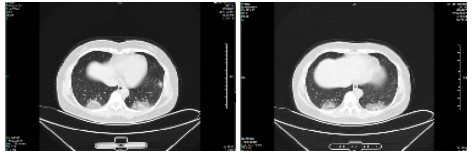

| 图 4 患者,男性,59岁,湖北籍,春节回乡探亲返沪,发热2 d入院,体温37.8℃, 乏力,既往体健。血白细胞总数及淋巴计数正常,甲型、乙型流感筛查阴性,新型冠状病毒核酸检测阳性。肺部CT提示双肺多发磨玻璃结节,病灶贴近胸膜伴支气管充气征及血管充血、增粗,可见部分纤维条索影 Fig 4 Case 4, male, 59 years old, born in Hubei Province, returned to Shanghai during the Spring Festival. He was hospitalized 2 days after fever, with a body temperature of 37.8℃ with fatigue. Normal WBC and lymphoid count, negative influenza A and B virus screening, positive novel coronavirus nucleic acid test. Lung CT showed multiple ground glass nodules in both lungs. The focus was close to the pleura, accompanied by bronchiectasis, hyperemia and thickening of blood vessels. Some fibrous bands could be seen |

| 图 5 患者,女性,44岁,沪籍,发病前10 d内有与确诊NCP患者接触史。出现发热,体温38.5℃,乏力,伴肌肉酸痛,既往体健。血白细胞总数及淋巴计数正常,甲型、乙型流感筛查阴性,新型冠状病毒核酸检测阳性。肺部CT提示双肺多发磨玻璃结节,病灶贴近胸膜伴支气管充气征及病变内血管充血、增粗 Fig 5 Case 5, female, 44 years old, born in Shanghai, had contact history with NCP patients within 10 days before the onset of the disease. Her body temperature was 38.5℃, with fatigue, muscle ache, previous physical fitness. Normal WBC and lymphoid count, negative influenza A and B virus screening, and positive novel coronavirus nucleic acid test. Lung CT showed multiple ground glass nodules in both lungs. The lesions were close to the pleura with bronchiectasis and congestion and thickening of blood vessels in the lesions |